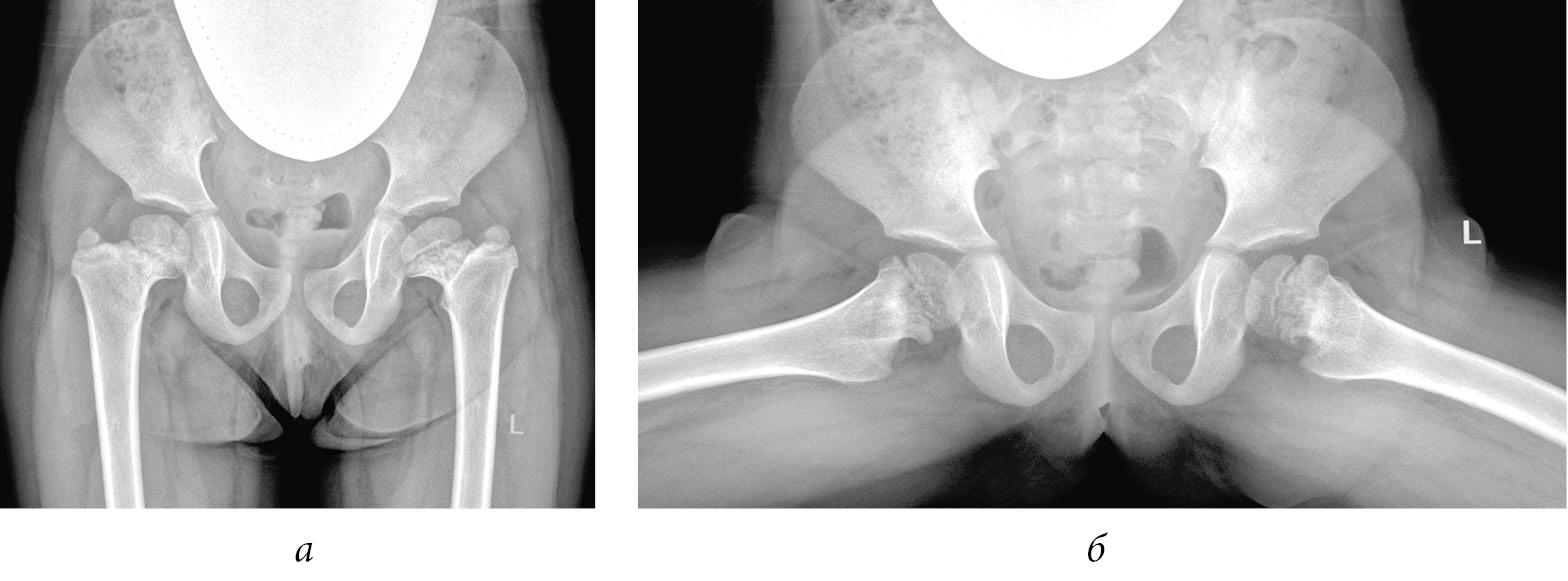

В нормальном тазобедренном суставе численно большим показателем из перечисленных является LTA. При выраженной гипертрофии большого вертела величина ATD принимала отрицательные значения, а показатель TTD становился больше LTA. Как видно на графике, это было характерно для подростков при сформировавшейся к окончанию роста деформации (рис. 9).

Рис. 9. Рентгенограмма пациента Б., 13 лет. Диагноз: «Состояние после консервативного лечения врожденного подвывиха бедра с двух сторон — последствия асептического некроза головки и шейки бедренной кости, высокое положение большого вертела». Вертельно-тазовый конфликт обусловлен выраженными анатомическими нарушениями, которые сопровождаются характерной клинической картиной и болевым синдромом

У детей с показателем ATD 0 и менее положительный симптом Тренделенбурга обнаружен в 87 % случаев. В дальнейшем у этих пациентов отмечались и клинические признаки вертельно-тазового конфликта — боль при отведении, разгибании и ротации бедра. При сравнении показателя ATD в норме и при патологии выявлена закономерность его уменьшения в динамике с ростом ребенка в пораженных тазобедренных суставах (рис. 10).